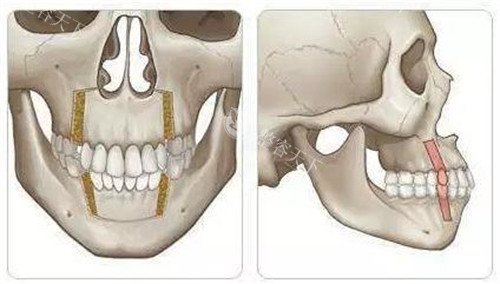

术中流程划线设计→消毒麻醉→小创口入路→骨骼重塑→止血缝合,全程心电监护。